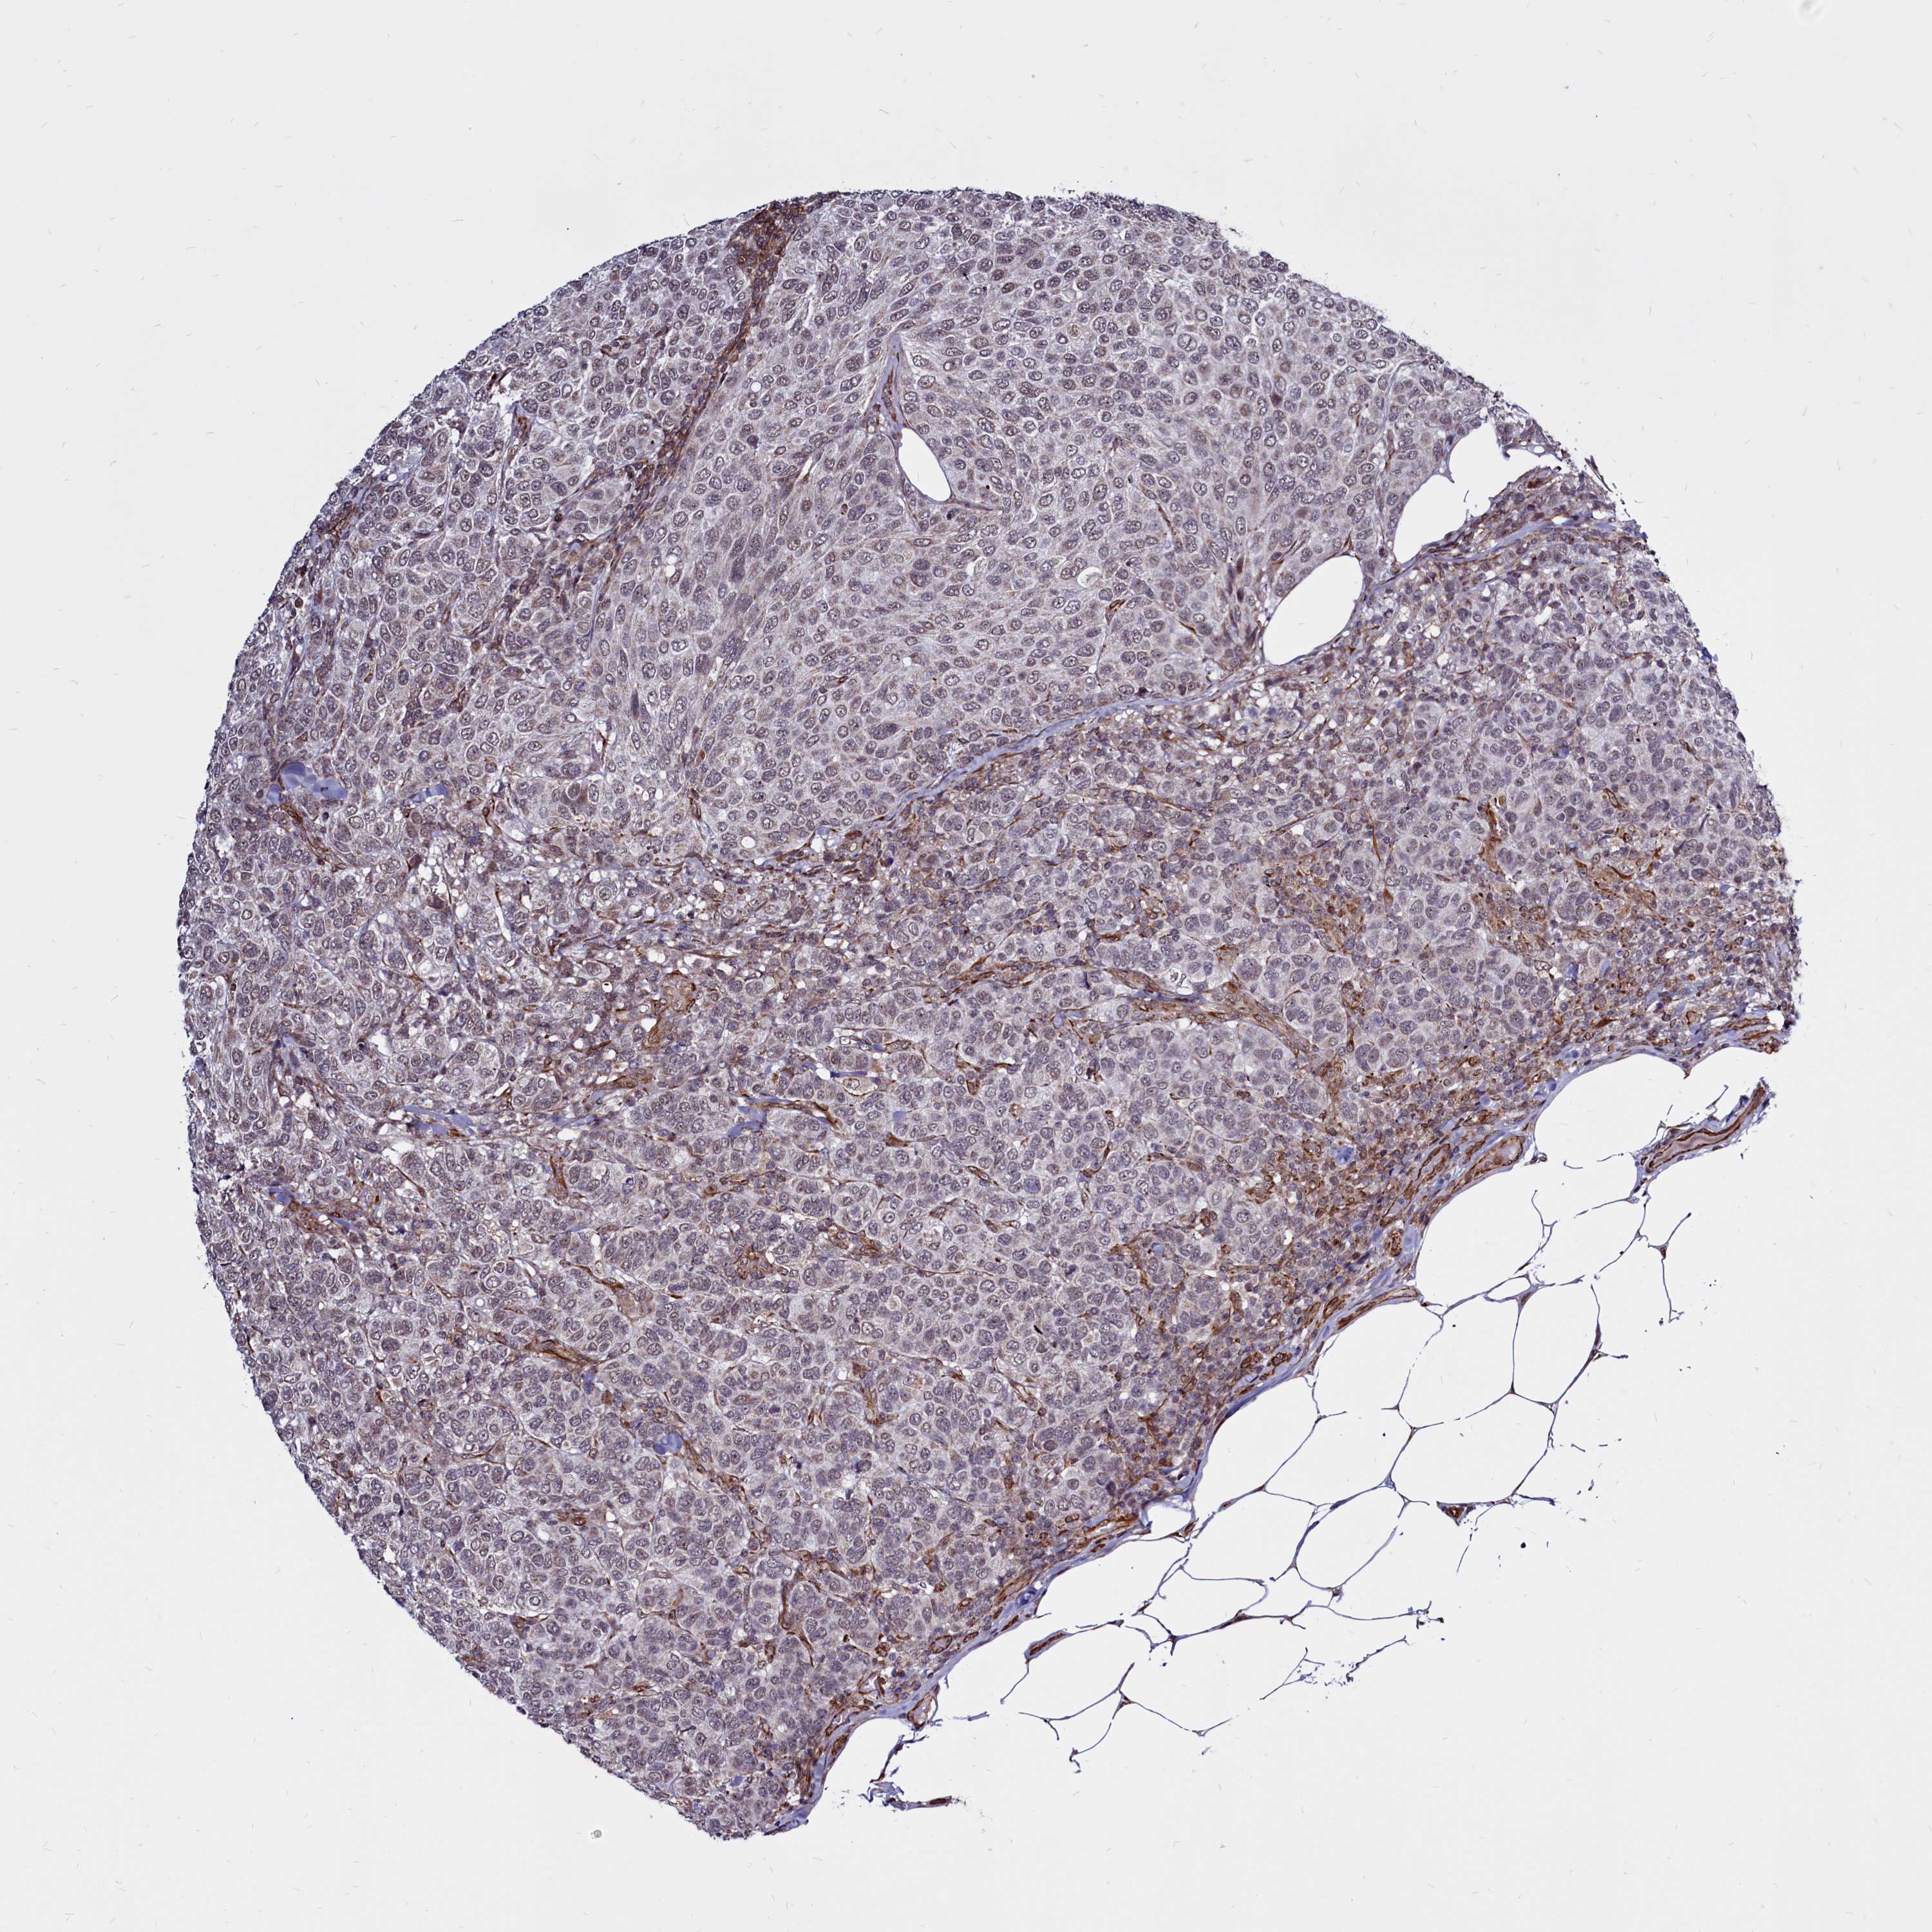

BRCA TCGA BRCA VALIDATION PROTEIN EXPRESSION

ANTIBODIES

AND

VALIDATION